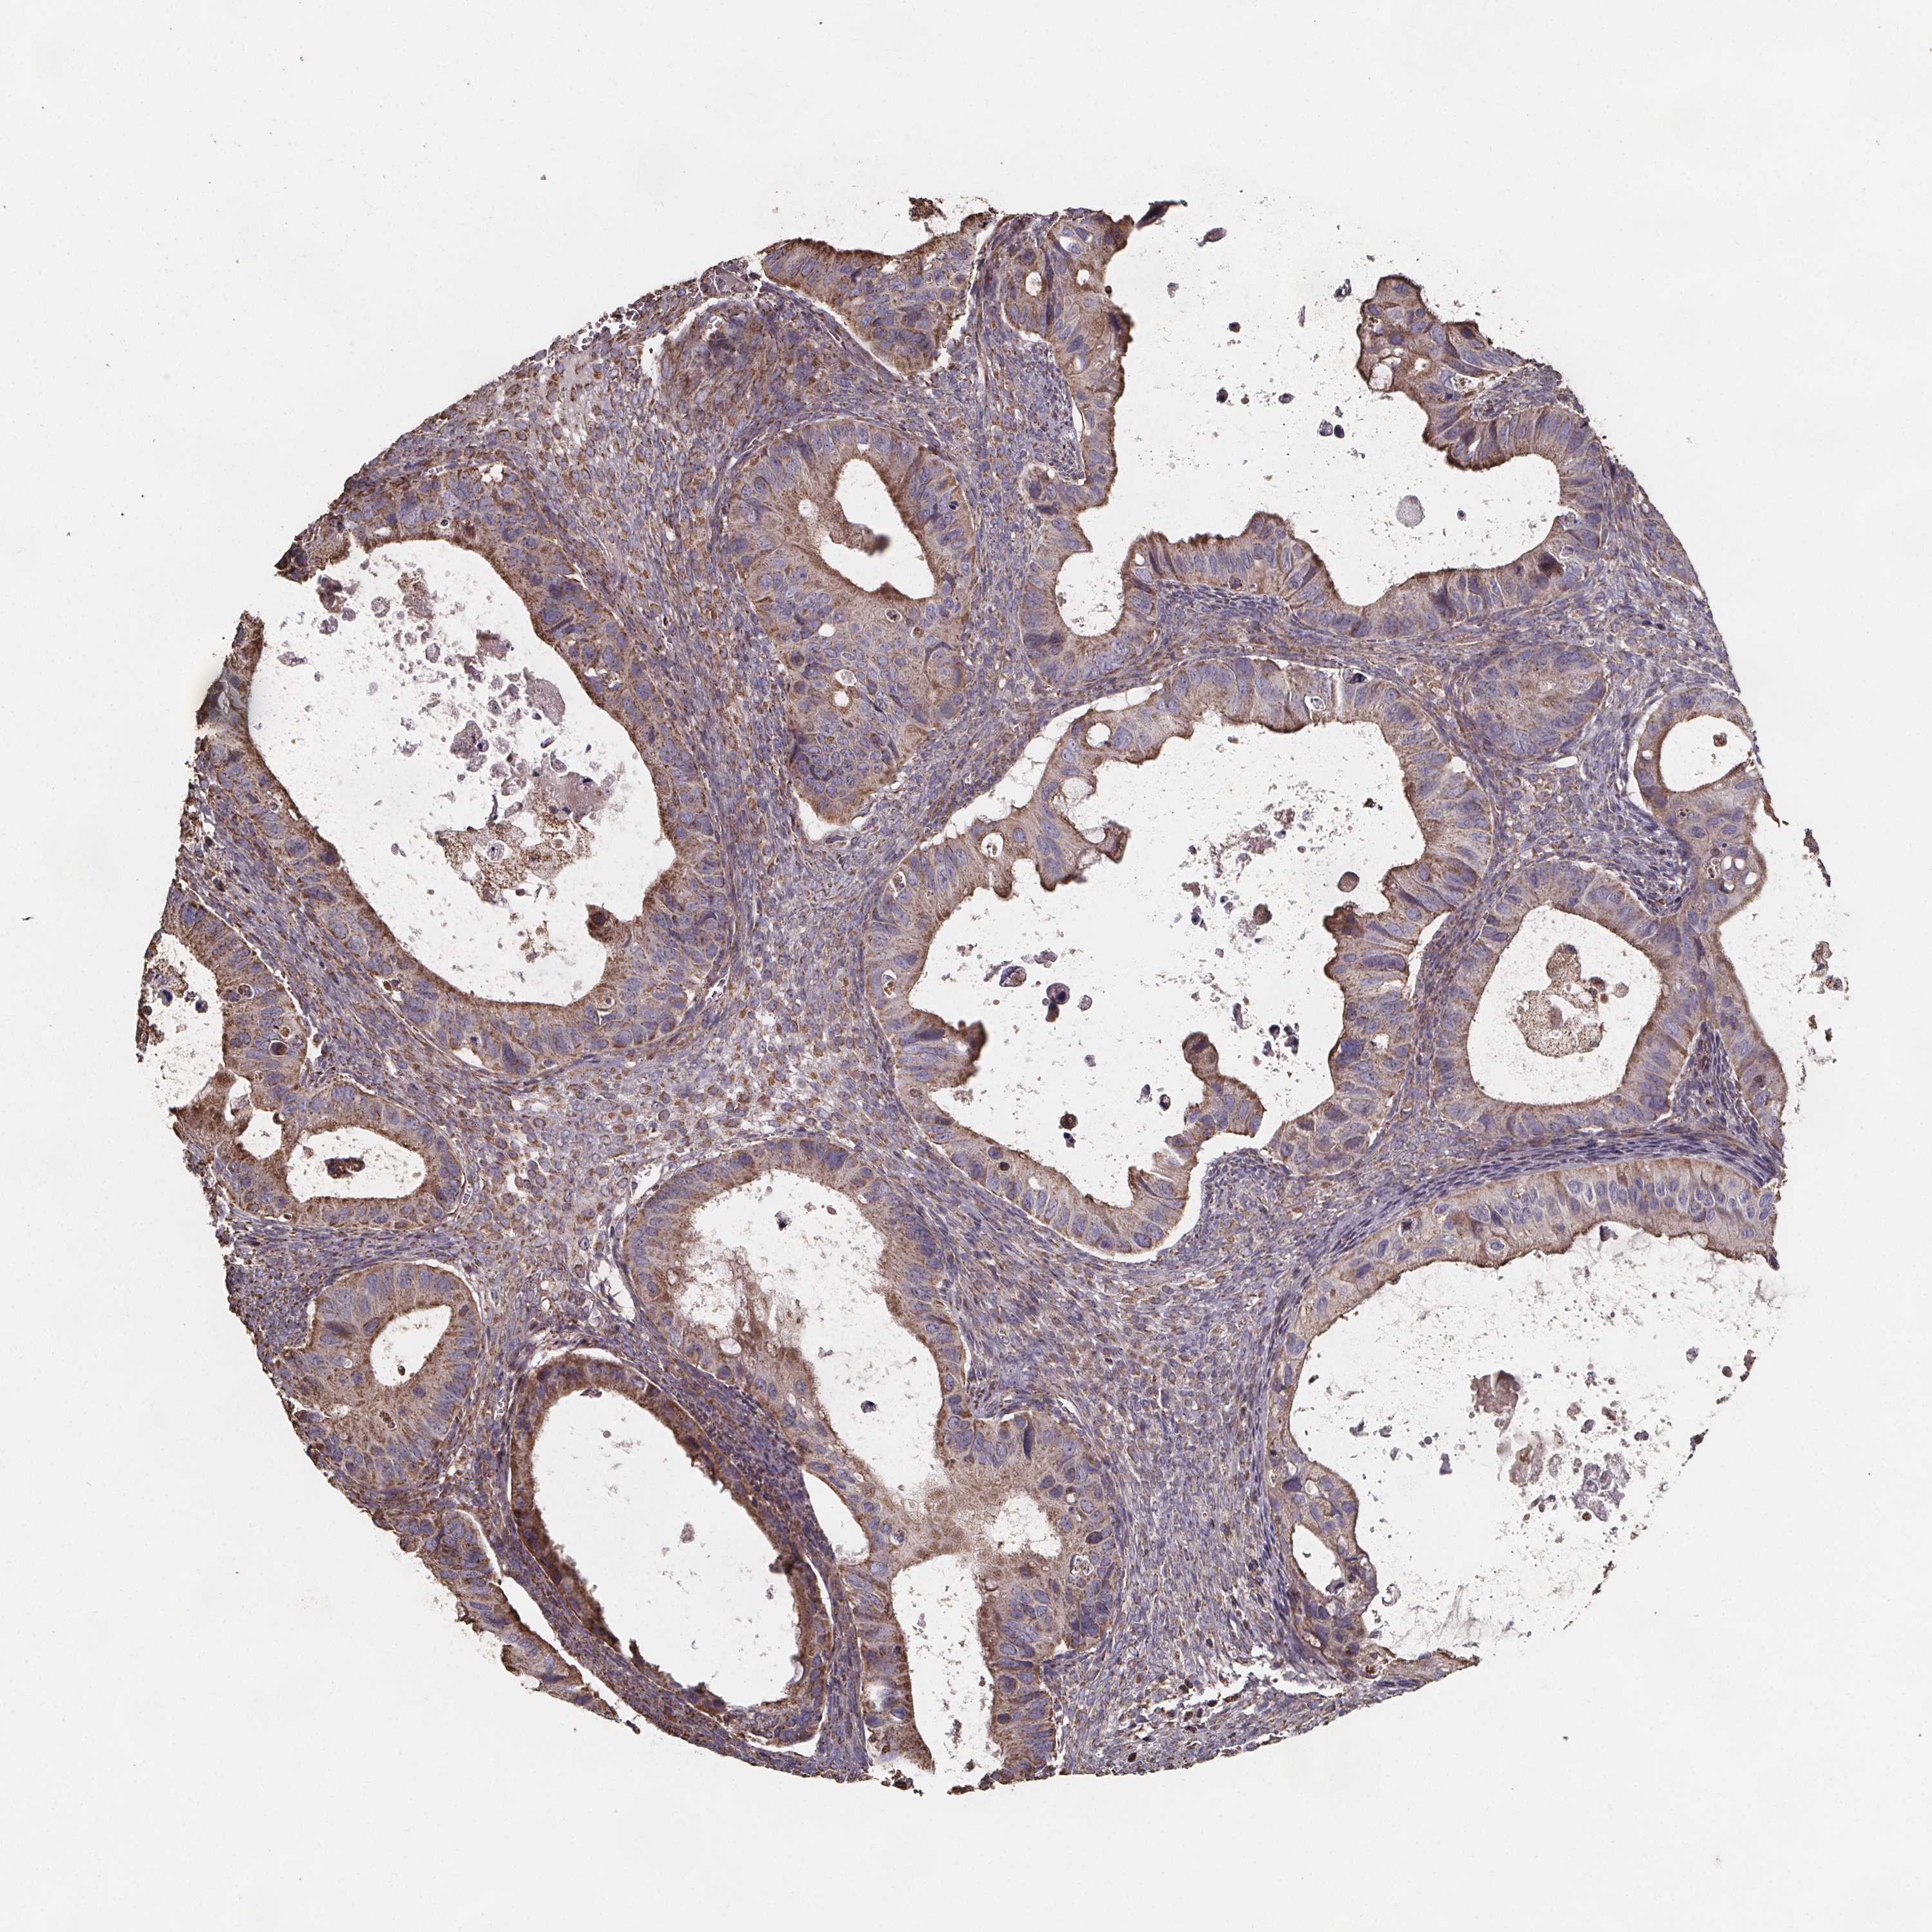

OVARIAN CANCER - Protein expressioni

A mouse-over function shows sample information and annotation data. Click on an image to view it in a full screen mode. Samples can be filtered based on level of antibody staining by selecting one or several of the following categories: high, medium, low and not detected. The assay and annotation is described here.

Note that samples used for immunohistochemistry by the Human Protein Atlas do not correspond to samples in the TCGA dataset.

Antibody stainingi

Antibody staining in the annotated cell types in the current human tissue is reported as not detected, low, medium, or high, based on conventional immunohistochemistry profiling in selected tissues. This score is based on the combination of the staining intensity and fraction of stained cells.

Each image is clickable and will lead to virtual microscopy that enables deeper exploration of all samples and also displays staining intensity scores, fraction scores and subcellular localization as well as patient and tissue information for each sample.

Antibody HPA064047

Staining

High

Medium

Low

Not detected

Intensity

Strong

Moderate

Weak

Negative

Quantity

>75%

75%-25%

<25%

None

Location

Nuclear

Cytoplasmic/membranous

Cytoplasmic/membranous,nuclear

Cystadenocarcinoma, serous, NOS

Cystadenocarcinoma, mucinous, NOS

Carcinoma, endometroid